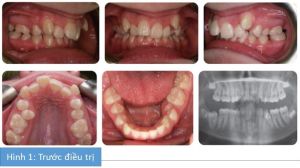

Phân tích case: Niềng răng thành công cho bệnh nhân nữ 14 tuổi bị hô

Bệnh nhân nữ 14 tuổi bị sai khớp cắn hạng II tiểu loại I trên nền xương hạng II trung bình với tỉ lệ theo chiều đứng giảm. Có tăng độ cắn chìa, cắn trùm tăng và hoàn toàn, và chen chúc nghiêm trọng ở cả 2 cung hàm. Tương quan răng hàm hạng II 2 bên và bị lệch đường giữa.

Mô tả khớp cắn

- Chen chúc nặng ở cung hàm dưới, R35 mọc 1 phần, R47 chưa mọc

- Các răng cửa dưới nghiêng trong và cả 2 răng nanh nghiêng xa

- Chen chúc nặng ở cung hàm trên. R15 mọc ra ở phía khẩu cái và cả 2 răng nanh hàm trên chen chúc phía ngoài.

- Độ cắn chìa tăng 9 mm (R11) nhưng R21 nghiêng trong.

- 2 răng nanh hàm trên nghiêng gần.

- Tương quan răng cửa là hạng II tiểu loại I với độ cắn chìa lớn ở R11.

- Tương quan răng hàm là hạng II 2 bên

- Đường giữa hàm dưới lệch trái và đường giữa hàm trên lệch phải do chen chúc răng.